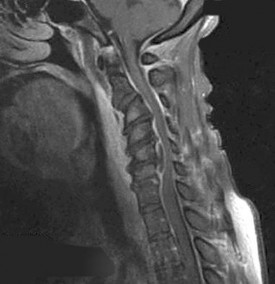

A 65-year-old male presents with progressive clumsiness in his hands, difficulty buttoning his shirt, and a wide-based gait. Physical exam reveals a positive Hoffmann's sign bilaterally.

MRI of the cervical spine demonstrates multilevel degenerative spondylosis with cord compression. Which of the following MRI findings is considered the strongest independent predictor of a poor neurologic recovery following surgical decompression?